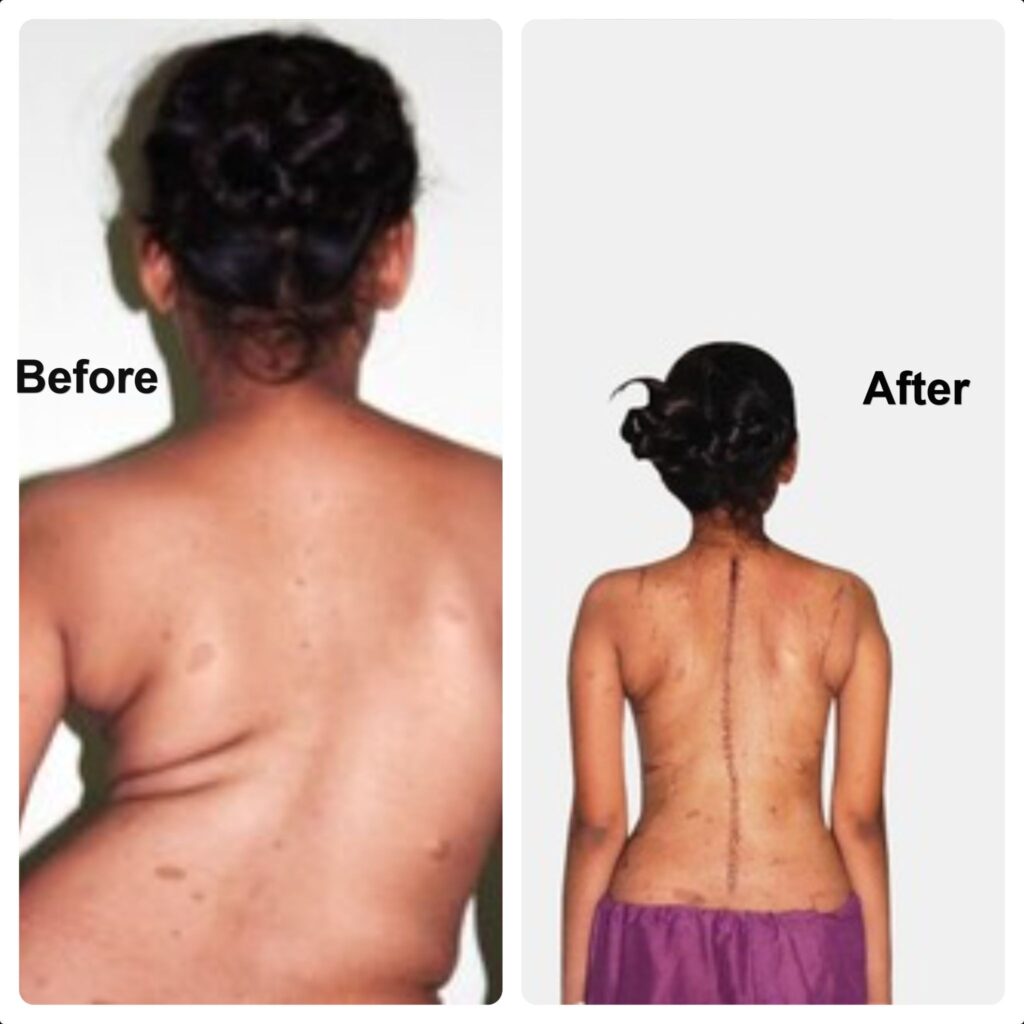

Scoliosis—Before and After Surgery